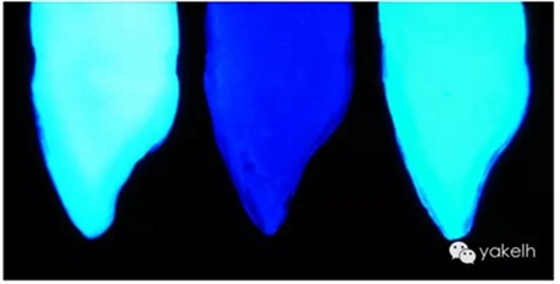

圖2.33天然牙、無熒光復合樹脂牙和熒光復合樹脂牙切片在紫外線下的影像。